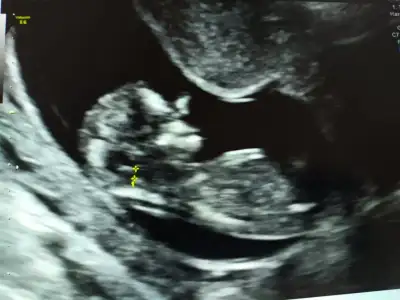

10 haftalık buUsg uygun değil sırtı görünüyorbaşka usg varsa paylaşın

Kız yönünde10 haftalık bu